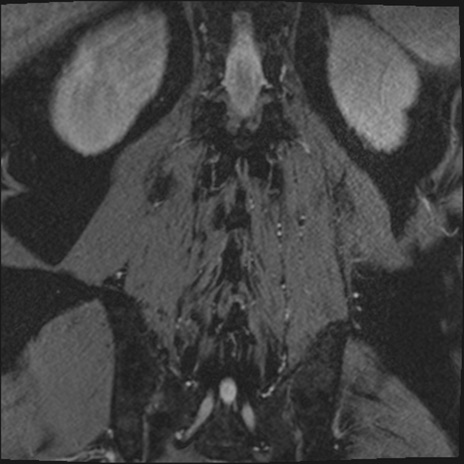

【整形】TIPS症例2 腰椎MRI 3D(冠状断像)

【症例】70歳代男性

【主訴】左下肢痛

【現病歴】2週間前くらいから腰痛、左下肢痛あり。左臀部から大腿、下腿外側のしびれが常時ある。歩行とともに同部位の痛みあり。

【身体所見】Lasegue70-/60+、Bragard-/±、PTR ±/±、ATR -/-、IP 5/5、TA 5/4、TS 5/5、EHL 右第1足趾なし/3、FHL 5/5、hypersthesia(-)、足背動脈触知良好

異常所見と診断は?